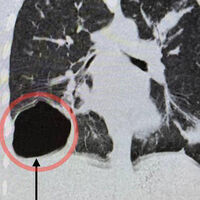

Врачи Московского областного центра охраны материнства и детства (МОЦОМД) спасли 17-летнего подростка с гигантской кистой с паразитами в легком. Об этом сообщили в пресс-службе Минздрава Московской области.

Юноша поступил в больницу с жалобами на недомогание, боль в правой половине грудной клетки и кашель. У него поднялась высокая температура. Обследование показало, что в правом легком находится крупная паразитарная киста.

«Ее размер был сопоставим с размером головы новорожденного ребенка. Киста образовалась из-за попадания в организм гельминта — эхинококка», — поделились медики.